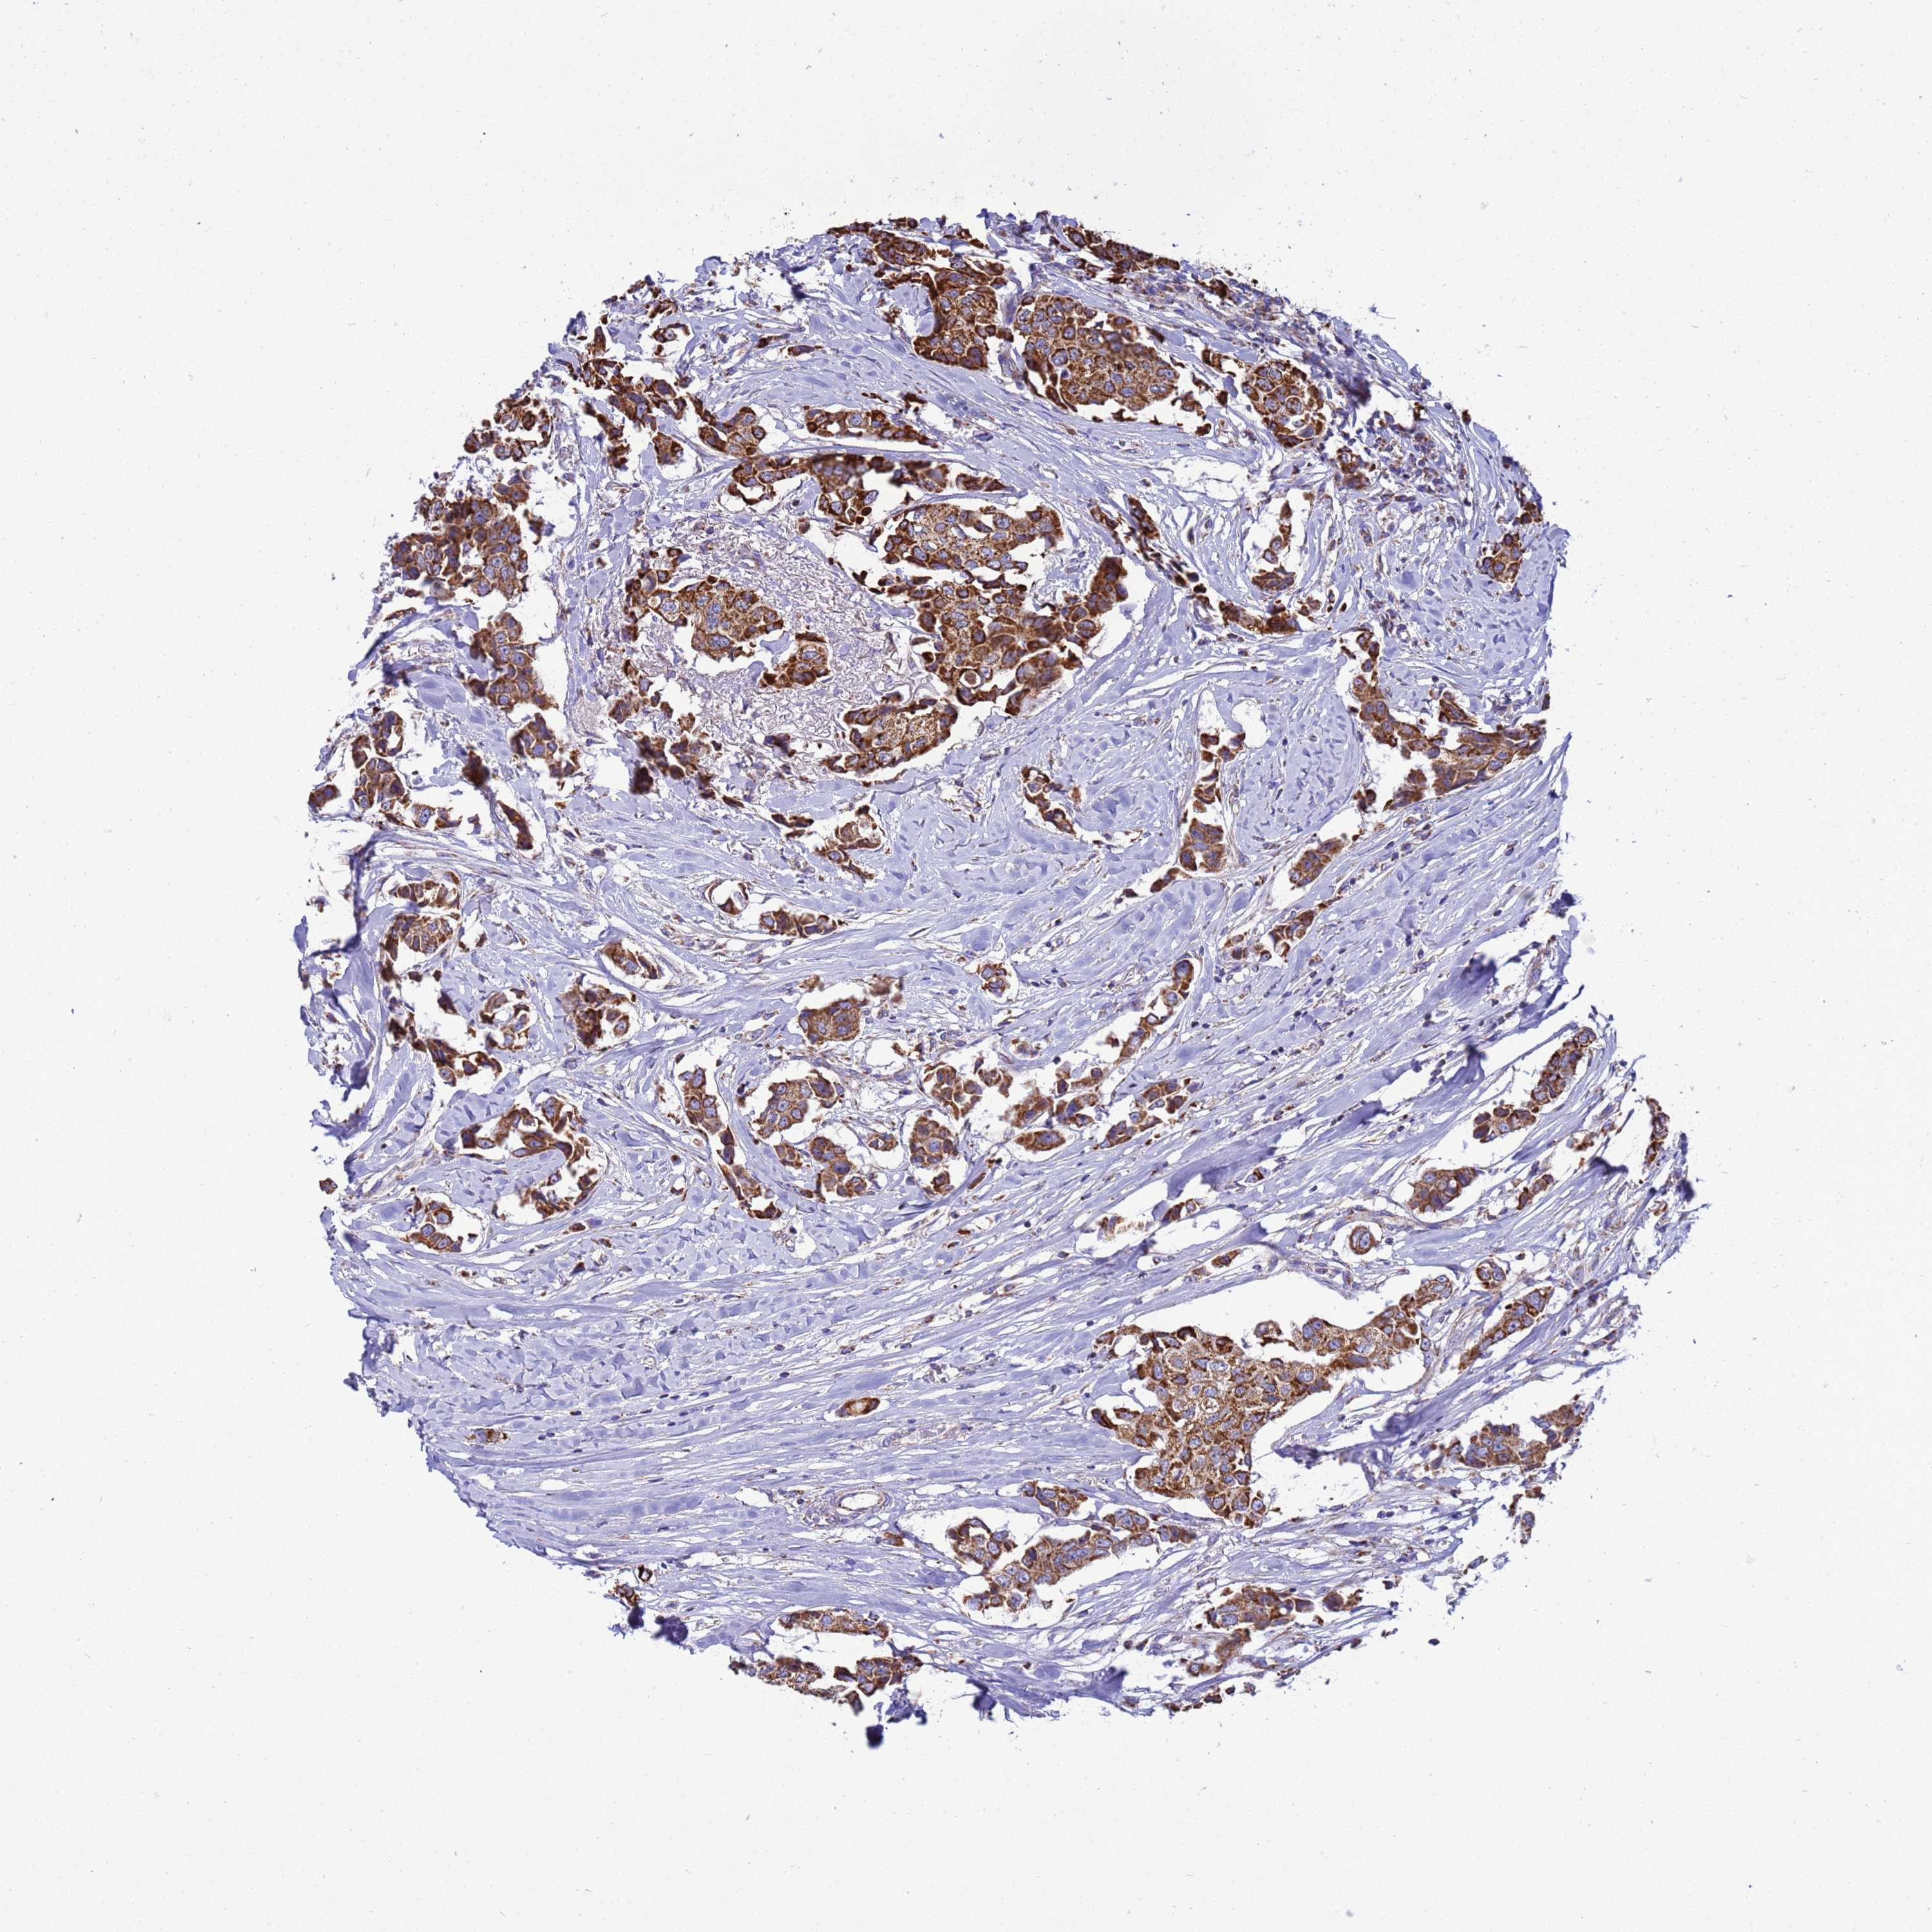

CANCER BREAST CANCER Show tissue menu

BRCA TCGA BRCA VALIDATION PROTEIN EXPRESSION